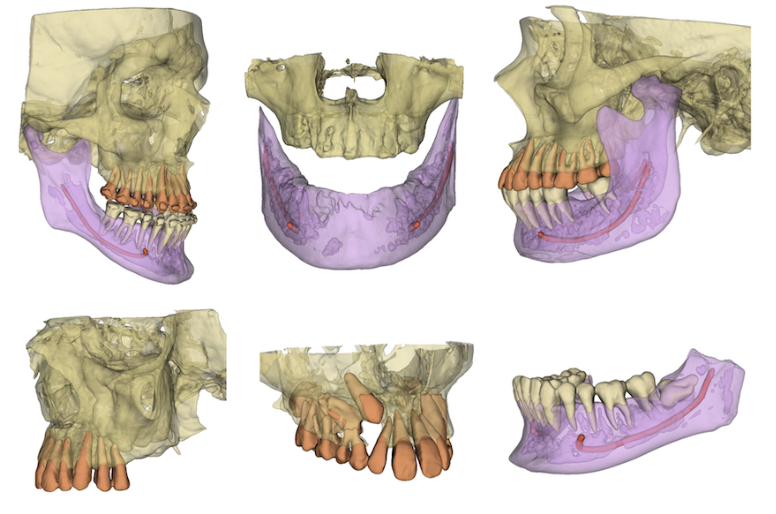

Coming Soon: Sugarbot 3D

Open-source research tool for dental CBCT. Load a volume and generate 3D segmentations of the maxilla, mandible, upper & lower teeth, and mandibular canal.

Built on 3D Slicer and DentalSegmentator. Not a medical device; not for clinical or diagnostic use.

Sugarbot 3D segmentation preview

CBCT segmentation

Automated masks for maxilla, mandible, upper & lower teeth, and the mandibular canal.